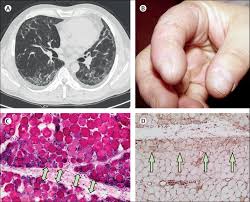

Cureus Autoantibody Negative Immune Mediated Necrotizing Myopathy Responds To Early And Aggressive Treatment A Case Report

Cureus Autoantibody Negative Immune Mediated Necrotizing Myopathy Responds To Early And Aggressive Treatment A Case Report from assets.cureus.com

Inclusion Body Myositis An Overview Sciencedirect Topics

Inclusion Body Myositis An Overview Sciencedirect Topics from ars.els-cdn.com